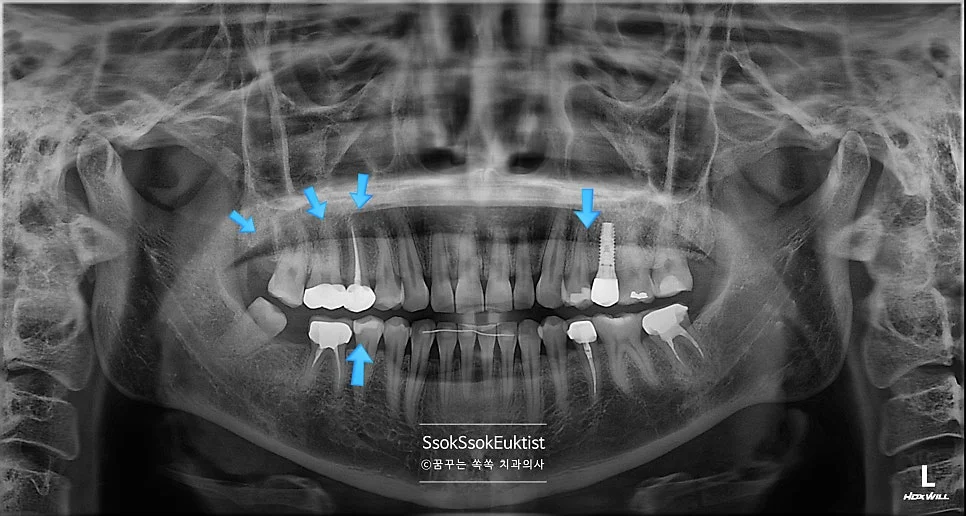

전체 구강 파노라마 X-ray — 처음 계획했던 치료가 두 번의 수면 마취를 통해 잘 마무리

처음 계획했던 치료가 두 번의 수면 마취를 통해 잘 마무리된 모습입니다.

- 2번 치아 → 충치가 있는 면과 기존 수복물을 모두 포함하는 치료 → 크라운 치료

- 1번 치아 → 2번 치아의 크라운 치료 시 인접한 면을 육안으로 확인 후, 치료가 필요한 만큼 충치가 있다면 레진으로 간단히 치료 (충치가 없으면 치료 X)

- 3번 치아 → 충치가 있는 면과 기존 수복물을 모두 포함하는 치료 → 크라운 치료

- 4번 치아 → 3번 치아의 크라운 치료 시 인접한 면을 육안으로 확인 후, 충치가 있다면 레진으로 간단히 치료

- 5번 치아 → 충치가 있는 면이 인접한 치아에 의해 막혀 있으므로 → 인레이 치료

- 6번 치아 → 충치가 있는 면이 인접한 치아에 의해 막혀 있으므로 → 인레이 치료

총 크라운 2개, 인레이 2개, 레진 가능성 치아 2개, 사랑니 발치 1개입니다.